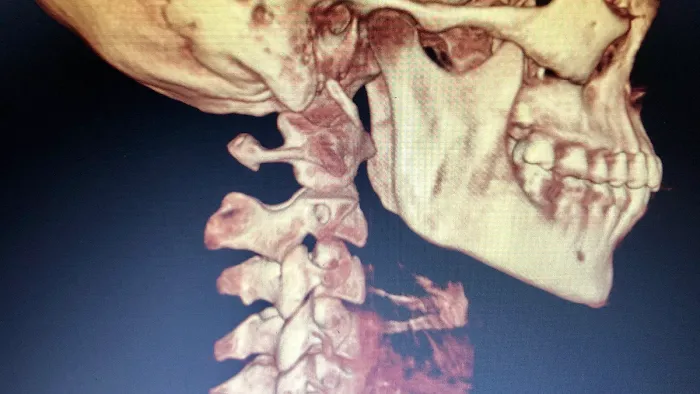

At Los Angeles Upper Cervical, the focus is on a unique and highly effective form of chiropractic care known as upper cervical chiropractic. This specialized approach centers on the crucial connection between the uppermost vertebrae of your spine (the atlas and axis) and your overall nervous system health. Misalignments in this delicate area can have far-reaching effects on your body, impacting everything from pain levels and mobility to neurological function and even your body's ability to heal itself. With a commitment to precision and a deep understanding of the body's intricate systems, Dr. Bello and his team offer a level of care that stands apart.

- Upper Cervical Chiropractic Adjustments: Precise, gentle adjustments focused on the atlas and axis vertebrae, aiming to correct misalignments that can impact the entire nervous system and body. These adjustments are often described as remarkably gentle yet profoundly effective.

- Detailed Scans and Diagnostics: Utilizing advanced imaging techniques to thoroughly assess the upper cervical spine and surrounding structures, guiding precise and effective treatment plans.

Jul 01, 2025 · Steve ImI came to see Dr Bello after a car accident last year. I was stiff and in a lot of pain. I wanted to make sure that if I saw someone after my accident they would know what they were doing and wouldn’t make me worse. Desperate for relief, I turned to Dr. Bello on a friend's recommendation. The accident affected my head, neck, back, hips, and threw off my jaw. His passion for upper cervical chiropractic care was evident from the start.Dr. Bello took detailed scans of my upper cervical vertebrae and head, which guided his treatment. He explained how neck displacements could impact the rest of my body. His targeted care began to alleviate my pain from day 1, including my jaw issues!! Nothing has ever helped my TMJ which was very much exacerbated atfter the accident.Beyond his chiropractic expertise, Dr. Bello collaborated with other practitioners. In the same building, I received acupuncture from Jessica at LaLuz Wellness, which helped with chronic pain and soft tissue injuries and trauma symptoms from the accident. Additionally, Jon Haupers LENS neurofeedback at Neurobalance addressed my TBI.This combination of treatments worked wonders. My pain lessened, my mobility improved, and I started to feel like myself again. Dr. Bello’s holistic approach, along with Jessica's and Jon's treatments, provided a comprehensive recovery plan.I would wholeheartedly recommend Dr. Bello . His genuine care, expertise, and dedication, combined with the collaborative efforts of his team, have made a profound difference in my life. I am incredibly grateful for their support and the thorough approach that has led to my healing.

Aug 16, 2024 · Heidi IreneI’ve been seeing Dr. Bello since January and I can’t say enough how much he has helped me. Prior to January, I was having horrible jaw pain that would last throughout the day and made eating a miserable experience. He did a 3D scan that showed the problem was actually my neck and explained how long it would take for it to improve with his adjustments.At first, I had to visit him twice a week because my neck was in such bad shape, but now I only have to see him once every three weeks and my neck muscles have gotten stronger and stabilized a lot. Still have a ways to go but I’m beyond happy with how these 7 months of care have gone.